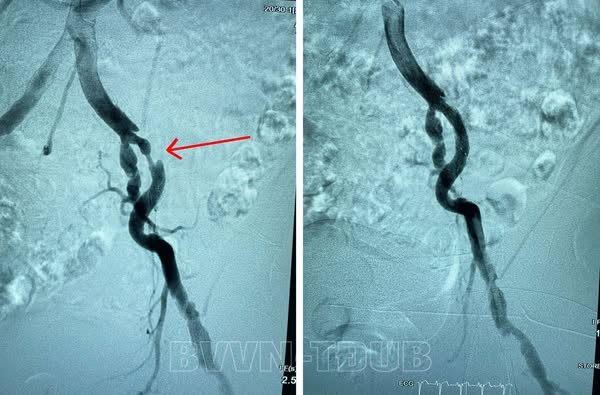

| Tắc động mạch chi trước và sau can thiệp - Ảnh BVCC |

Ngay khi tiếp nhận người bệnh, tiến hành siêu âm mạch các bác sĩ phát hiện người bệnh có tình trạng hẹp, tắc động mạch chi dưới. Hình ảnh chụp mạch số hóa xóa nền DSA cho thấy tình trạng hẹp động mạch chậu ngoài bên trái, vị trí hẹp nhiều nhất là 90%.

Nhận định đây là trường hợp bệnh nặng, phức tạp, xơ vữa gây chít hẹp động mạch với nguy cơ tiến triển nặng, bác sĩ tiến hành hội chẩn và quyết định thực hiện phương án tối ưu nhất bằng can thiệp nong bóng và đặt stent động mạch chậu cho người bệnh.

Với việc làm chủ kỹ thuật, các bác sĩ đã tiến hành can thiệp cho người bệnh trong khoảng hơn 1 giờ đồng hồ. Sau can thiệp, sức khỏe người bệnh ổn định. Chụp mạch đánh giá sau can thiệp cho thấy các vị hẹp, tắc được tái thông, người bệnh hết tình trạng đau nhức, tê bì chân trái.